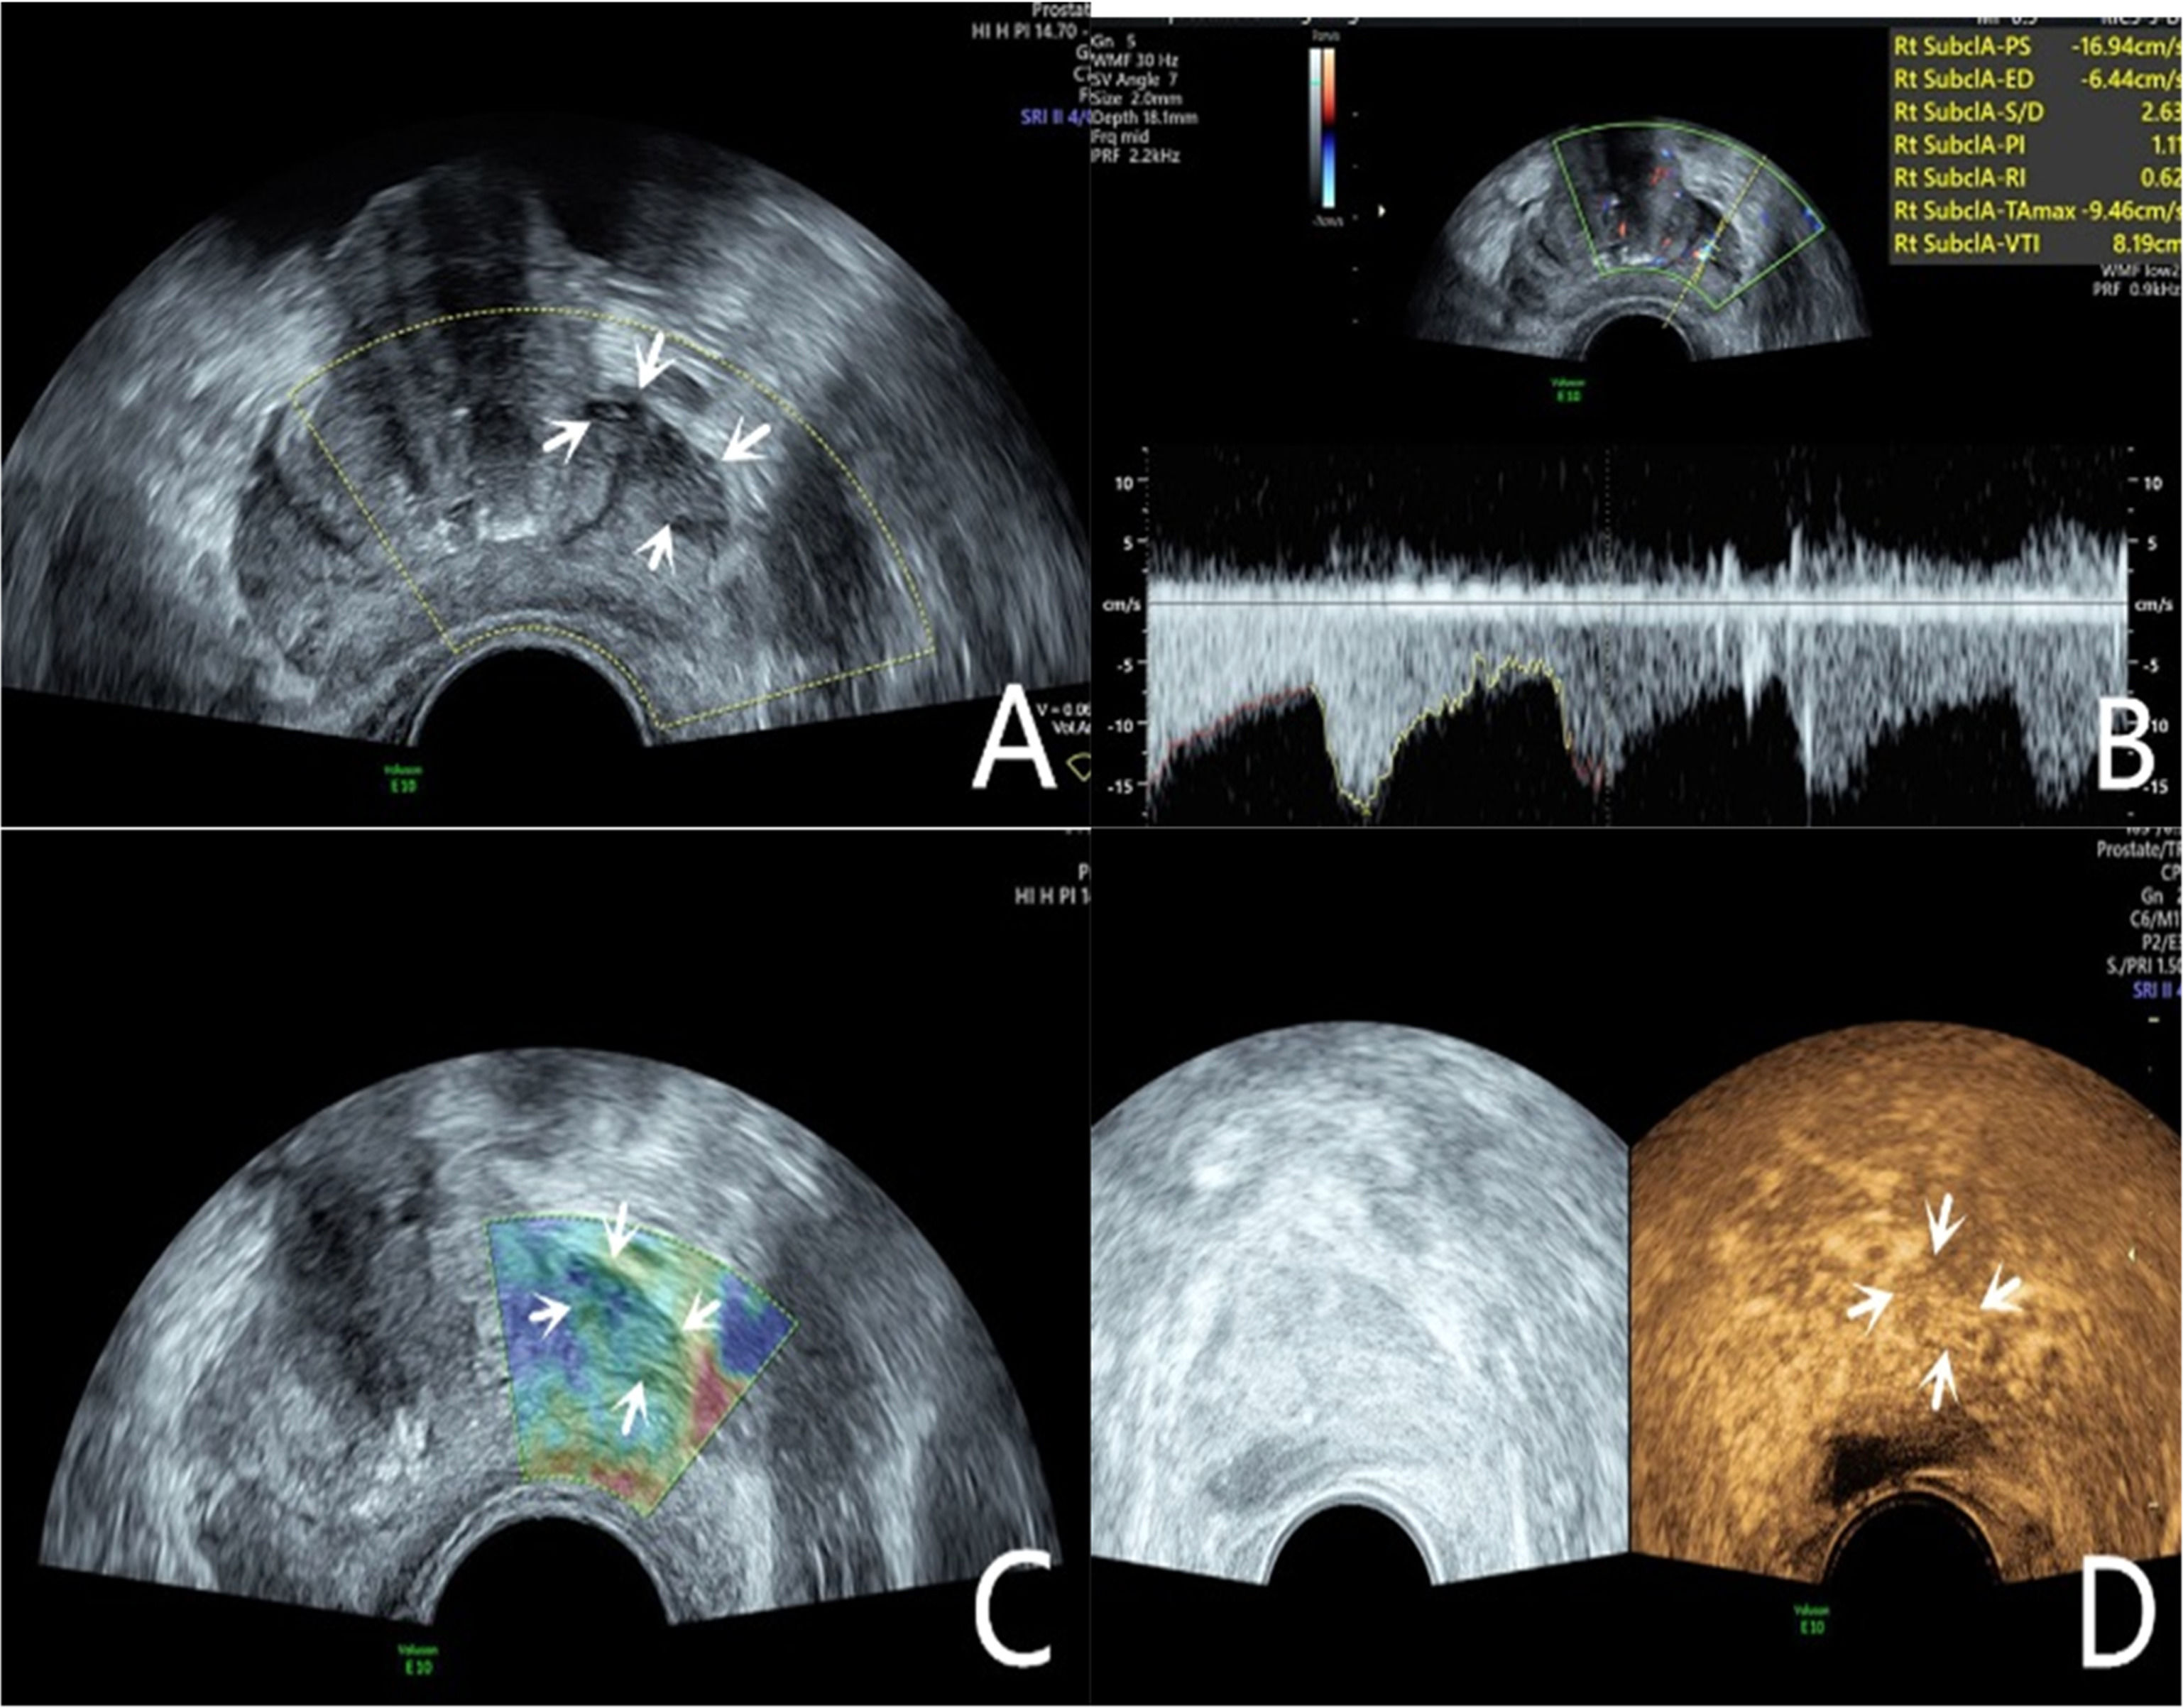

The lesion was a hypoechoic nodule in the outer glands of the prostate’s right lobe (A, arrow). The lesion appeared on CDU with rich blood flow (B). The operator used the endocavitary transducer to alternate between compressing and decompressing the lesion, which appeared mostly blue on TRTE (C). A hypoechoic nodule appeared on CEUS as a hypervascular nodule with hyperenhancing pattern (D).

Grayscale ultrasound examinationTransrectal GSU was routinely performed using a GE Voluson E10 ultrasound system (GE Healthcare, Milwaukee, WI, USA) with a 3.5‒8 MHz rectal convex array probe (RIC 5–9-D). Before the examination, the patients were asked to empty their bowels and were positioned in a left lateral decubitus position. Then, a sonographer inserted the probe into the patient's rectum and preliminarily evaluated the shape, size, internal parenchymal echo, and integrity of the capsule of the prostate through multiple views, such as longitudinal and transverse sections. The criteria for GSU were as follows: a hypoechoic lesion in the prostate parenchyma was suspiciously positive, and isoechoic or hyperechoic lesions were considered negative (Fig. 1A; Fig. 2A).10

The CDU/PDU examination of suspicious areas followed the grayscale ultrasound examination described above. The richness of blood flow in the parenchyma and the presence or absence of abnormal blood flow branches were observed. The criteria for Doppler ultrasonography were as follows: areas with rich blood flow or multiple abnormal blood flow branches compared with the surrounding normal prostate tissue were suspiciously positive, and areas with consistent blood flow or reduced blood flow compared to the surrounding normal tissue were considered negative (Fig. 1B; Fig. 2B).14

Transrectal real-time tissue elastographyBy engaging the dual display function for grayscale images and elastic images at the same time, TRTE examination on the hypoechoic area from GSU and the area with abnormally increased blood flow from Doppler ultrasound was performed. The suspicious area was placed in the sampling frame, and the probe was used to regularly and gently press the gland 1‒2 times/second with a pressure index of approximately 4. The optimal force and frequency of the manual compressions of the prostate were monitored by the visual color bar and waveform indicators. The images were frozen and stored after 3‒5 stable waveforms appeared in the elastogram. Different colors on the TRTE elastogram marked different densities of prostate tissue, with blue indicating hard tissues and red indicating soft tissues. PCa is stiffer than normal prostate tissue and often appears blue on TRTE images due to increased cell density, microvascularization, and collagen deposition from the matrix reaction. The criteria for TRTE were as follows: a blue area > 50 % in the nodule was suspiciously positive, and an area ≤ 50 % was considered negative (Fig. 1C; Fig. 2C).15

Contrast-enhanced ultrasound examinationThe microbubble suspension-based contrast agent SonoVue (Bracco Imaging SpA, Milano, Italy, 2.4 mL) was fully mixed with 5 mL of 0.9 % NaCl solution and was administered intravenously. The examination was started after the injection of the microbubble suspension and performed with a mechanical index of 0.2. Data such as contrast enhancement time, enhancement intensity, and contrast agent disappearance time in the suspiciously marked lesions of the prostate were recorded synchronously. After the contrast agent completely dissipated, the sonographer repeated the same examination again. The criteria for CEUS were as follows: early hyper enhancing areas in the prostate were suspiciously positive, and areas of simultaneous or late, isoenhancing or hypo-enhancing areas were considered negative (Fig. 1D; Fig. 2D).16 The results of all the above examinations were judged independently by two sonographers. Both sonographers are professors of ultrasonic diagnostics. The data used for the later logistic regression analysis were the results from only a senior experienced sonographer. The data for the repeatability test were additionally obtained from another sonographer with similar clinical experience who examined a random sample of patients compared to the previous sonographer.